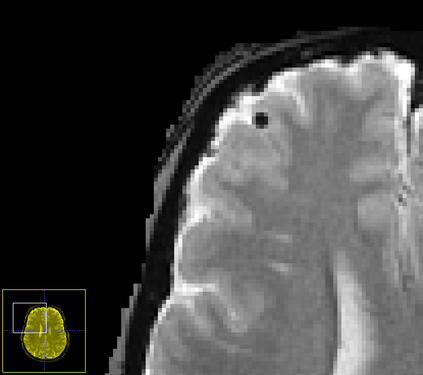

Imaging markers of cerebral small vessel disease provide valuable information on brain health, but their manual assessment is time-consuming and hampered by substantial intra- and interrater variability. Automated rating may benefit biomedical research, as well as clinical assessment, but diagnostic reliability of existing algorithms is unknown. Here, we present the results of the \textit{VAscular Lesions DetectiOn and Segmentation} (\textit{Where is VALDO?}) challenge that was run as a satellite event at the international conference on Medical Image Computing and Computer Aided Intervention (MICCAI) 2021. This challenge aimed to promote the development of methods for automated detection and segmentation of small and sparse imaging markers of cerebral small vessel disease, namely enlarged perivascular spaces (EPVS) (Task 1), cerebral microbleeds (Task 2) and lacunes of presumed vascular origin (Task 3) while leveraging weak and noisy labels. Overall, 12 teams participated in the challenge proposing solutions for one or more tasks (4 for Task 1 - EPVS, 9 for Task 2 - Microbleeds and 6 for Task 3 - Lacunes). Multi-cohort data was used in both training and evaluation. Results showed a large variability in performance both across teams and across tasks, with promising results notably for Task 1 - EPVS and Task 2 - Microbleeds and not practically useful results yet for Task 3 - Lacunes. It also highlighted the performance inconsistency across cases that may deter use at an individual level, while still proving useful at a population level.